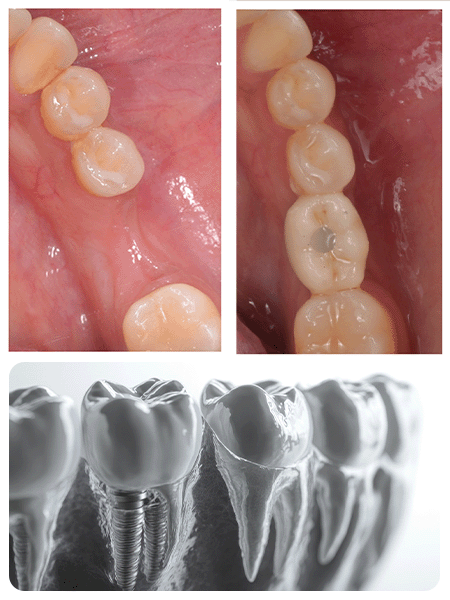

A dental implant is a small titanium screw that is surgically placed into the jawbone, serving as a replacement for a missing tooth root. It provides a secure and durable foundation for a natural-looking replacement tooth, restoring both function and appearance.

At our smile gallery, we showcase the stunning results of our Digital Smile Design. See transformations from single-tooth restorations to full mouth reconstructions, each tailored to enhance natural beauty and facial harmony

Straumann and Nobel Biocare Implant systems known for their reliability and long-term success.